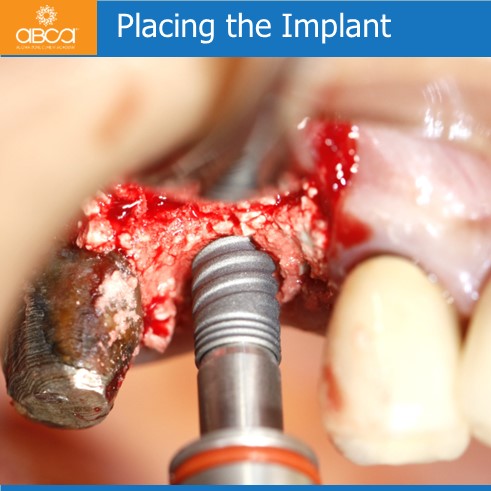

The patient is a 50 year old female with severe posterior maxillary atrophy. She came in for a posterior maxillary implant procedure. Implants were placed using Augma Lift™ Kit B.

Sinus lift with Augma Lift™ Kit B with 4-5 mm sub sinus bone height.

Sinus lift with Augma Lift™ Kit B with 4-5 mm sub sinus bone height. A young woman came to replace the missing first maxillary molar with moderate atrophy.

Sinus lift with Augma Lift™ Kit B in a case with 5 mm sub sinus bone height.

Sinus lift with Augma Lift™ Kit B in a case with 5 mm sub sinus bone height. The patient came for implant treatment in the region of teeth #16 (3)…